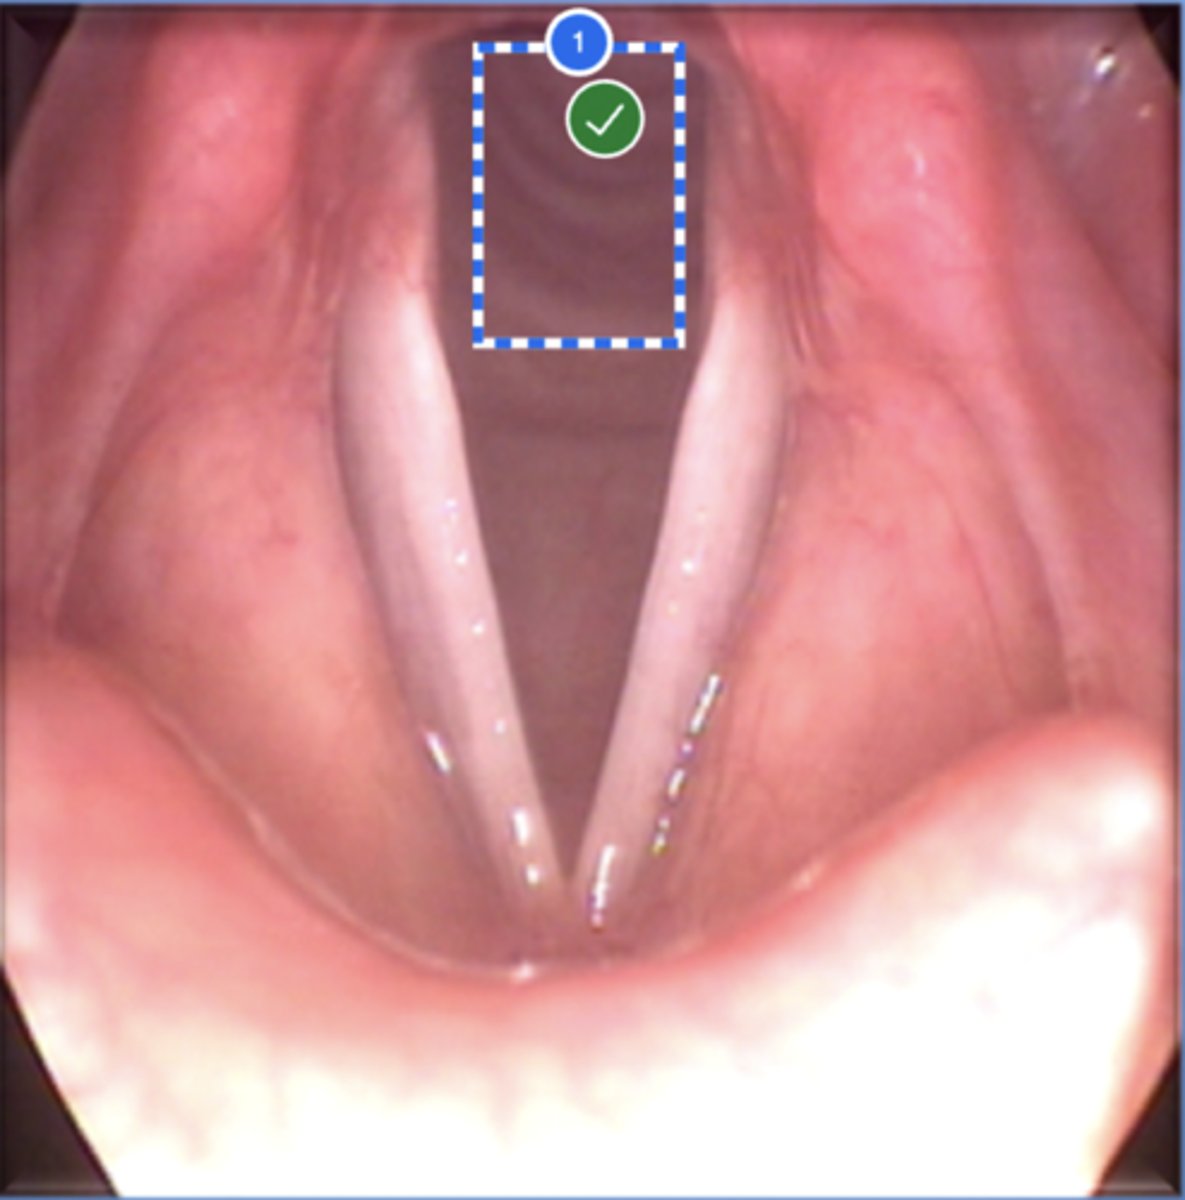

Label left true vocal fold (superior view)

Label right false vocal fold (superior view)

label right arytenoid (superior view)

Label trachea (superior view)

Label epiglottis (superior view)

Label right true vf (superior view)